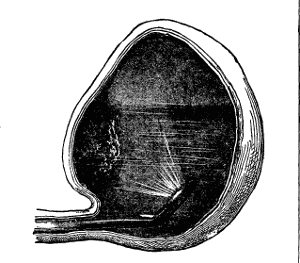

| XII. SURGERY.—Papillomatous Tumor of the Bladder, demonstrated by Means of Lister's Electro-cystoscope.—By F. N. Otis, M.D.—An interesting instance of the use of an exploratory electric light.—2 illustrations. | 10354 |

| Tumors of the Bladder Diagnosed by Means of the Electro-Endoscopic Cystoscope.—By Dr. Max Nitze.—The same general subject in further detail, giving the German practice.—5 illustrations. | 10353 |